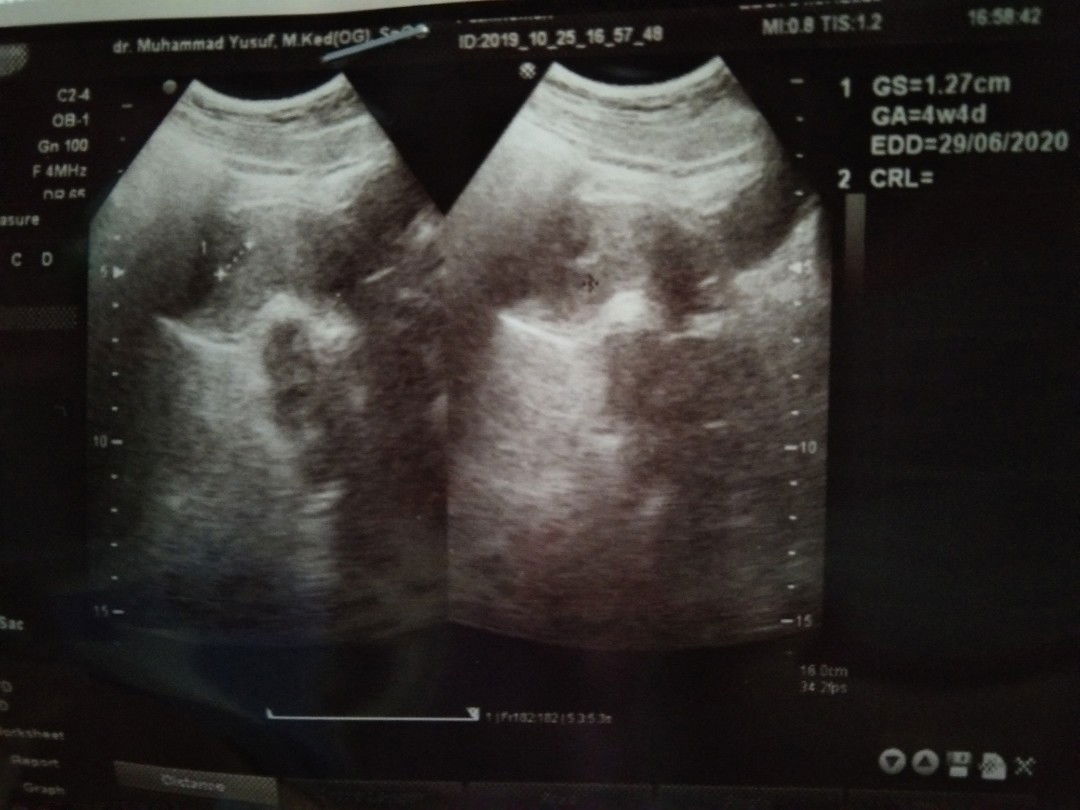

Saya heran, kok dari USG, kandungan saya masih 4 minggu 4 hari ya? Padahal klu untuk ukurannya, klu saya sesuaikan dengan aplikasi ini, seharusnya saya sudah minggu ke-7 . Saya HPHT tanggal 6 september 2019. Lagian, klu 4 minggu 4 hari, klu saya cocokkan dengan aplikasi ini, ukuran kantung janinnya belum ada, tapi di usg, sudah 1,27. Yang mana yang betul ya??? Saya jadi tidak tau perkembangannya sudah minggu ke berapa